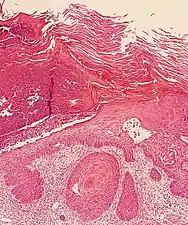

Histopathologically, the epidermis in cSCC in situ (Bowen's disease) will show hyperkeratosis and parakeratosis. There will also be marked acanthosis with elongation and thickening of the rete ridges. These changes will overly keratinocytic cells which are often highly atypical and may in fact have a more unusual appearance than invasive cSCC. The atypia spans the full thickness of the epidermis, with the keratinocytes demonstrating intense mitotic activity, pleomorphism, and greatly enlarged nuclei. They will also show a loss of maturity and polarity, giving the epidermis a disordered or "windblown" appearance.

Two types of multinucleated cells may be seen: the first will present as a multinucleated giant cell, and the second will appear as a dyskeratotic cell engulfed in the cytoplasm of a keratinocyte. Occasionally, cells of the upper epidermis will undergo vacuolization, demonstrating an abundant and strongly eosinophilic cytoplasm. There may be a mild to moderate lymphohistiocytic infiltrate detected in the upper dermis.[12]

Histopathology of squamous-cell carcinoma in situ (black arrow), compared to normal skin, showing marked atypia.

Squamous-cell carcinoma in situ, showing prominent dyskeratosis and aberrant mitoses at all levels of the epidermis, along with marked parakeratosis.[12]